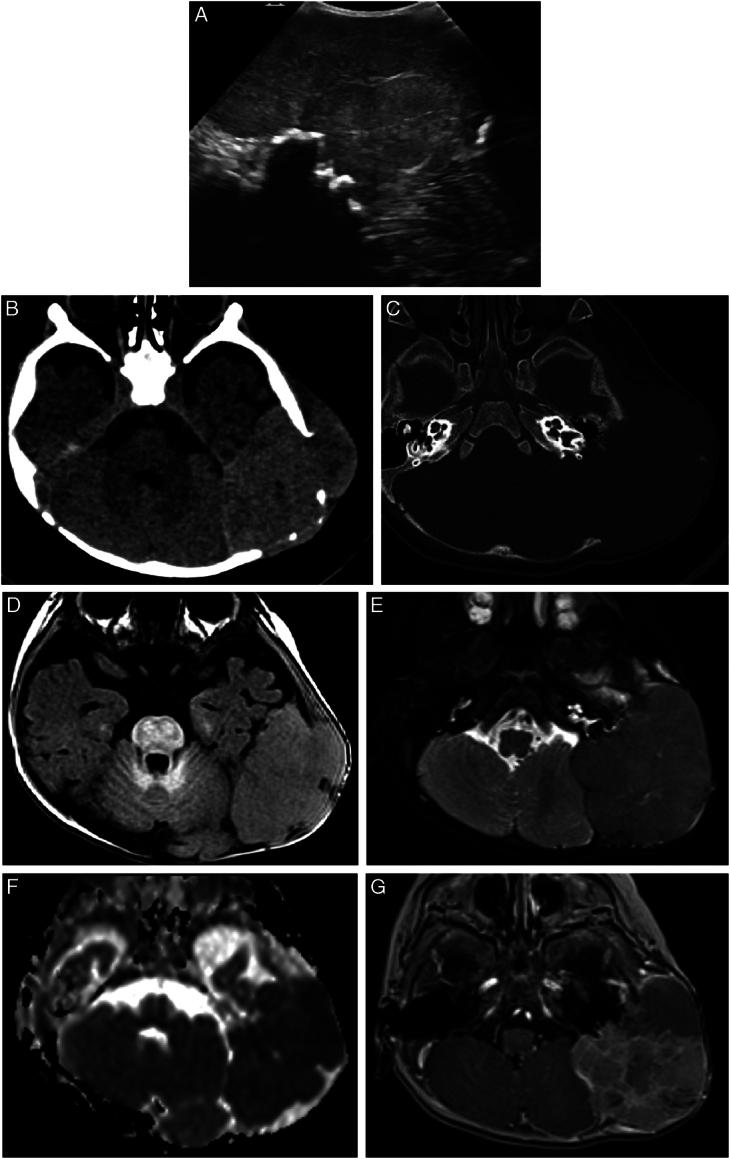

Juvenile Xanthogranuloma (JXG) is a non-Langerhans cell histiocytosis, occurring mainly in infancy. With an extracutaneous lesion, its diagnosis is difficult, because of a wide clinical spectrum. Here we demonstrate and characterize imaging features of 11 patients with JXG of the head and neck in various locations.

We recorded clinical data and reviewed all imaging studies of 11 patients with JXG of the head and neck. Ultrasonography (US) alone was performed in 1 patient; MRI alone in 6 patients; US and MRI in 1 patient; and US, CT, and MRI in 3 patients. We evaluated the following characteristics in all studies: location and number of lesions, echogenicity and vascularization on US, density on CT, signal intensity on T 1 - and T 2 -weighted images, ADC and enhancement on MRI, and tumor boundaries and bone involvement.

RESULTS

Lesions were well-defined in 9 cases, and bone erosion was present in 2. On US, lesions were hypoechoic or hyperechoic and with or without vascularization. On CT, lesions were hyper-dense, with no calcification. On MRI, lesions were mildly hyper-intense or iso-intense on T 1 -weighted images in 8 of 9 patients, hypo-intense on T2-weighted images in 7 of 10, low ADC in 7 of 9, and enhancement in 7 of 7.

CONCLUSIONS

The diagnosis of extra cutaneous JXG may be proposed, with the following suggestive criteria: age < 1 year, well-defined lesion, mild hyper-intensity on T 1 -weighted images, hypo-intensity on T 2 -weighted images, low ADC, enhancement, and possible adjacent bone involvement.

幼年黄色肉芽肿(JXG)是非朗格汉斯细胞组织细胞增生症,主要发生在婴儿期。由于临床表现广泛,伴有皮肤外病变,其诊断较为困难。在此,我们展示并描述了 11 例头颈部不同部位 JXG 的影像学特征。

材料和方法

我们记录了 11 例头颈部 JXG 患者的临床资料,并回顾了所有影像学检查。1 例仅行超声检查,6 例行 MRI 检查,1 例同时行超声和 MRI 检查,3 例同时行超声、CT 和 MRI 检查。我们评估了所有研究的以下特征:病变位置和数量、超声的回声和血管化、CT 的密度、T1 和 T2 加权图像的信号强度、MRI 的 ADC 和增强、肿瘤边界和骨受累。

结果

9 例病变边界清楚,2 例有骨侵蚀。超声检查显示病变呈低回声或高回声,伴或不伴血管化。CT 显示病变呈高密度,无钙化。MRI 显示 9 例中 8 例 T1 加权图像呈轻度高信号或等信号,10 例中 7 例 T2 加权图像呈低信号,9 例中 7 例 ADC 低,7 例增强。

结论

对于皮肤外 JXG,以下提示性标准可能有助于诊断:年龄<1 岁,边界清楚的病变,T1 加权图像呈轻度高信号,T2 加权图像呈低信号,ADC 低,增强,可能伴有相邻骨受累。